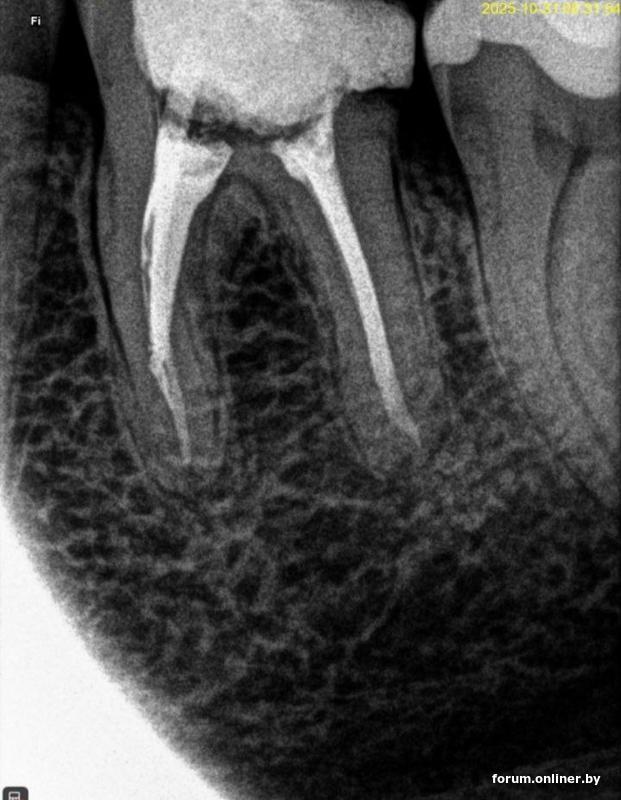

Здравствуйте. Подскажите пожалуйста, по состоянию зуба и каналов. После перелечтванния из-за инструмента в канале, зуб потемнел с одной стороны. Врач говорит, что все ок, потемнение это нормально, инструмент достали, канал перепломбировки хорошо. Это фото сделано после перелечивания. Человек сейчас по работе не в Беларуси, по этому п

олучить второе мнение вживую сложно. Фото из самой клиники, которые прислали, не очень информативны. Это сделано в другой клинике по своей инициативе. Смущает потемнение внутри зуба между корнями и пломбой временной. Следующий этап это коронка, но не понятно модно ли на все это ее ставить. Заранее спасибо за ответ.

Вот это фото из клиники, которое прислали по запросу, не ясно какое до перепломбировки, какое после. Вот так и выслали, как фото с компьютера. Может будет полезно. Но первое с потемнением более свежее, а это старше где то сразу после лечения или в процессе или до, врач не уточнил и дат на фото нет.

Вот места на актуальном фото которые особенно интересуют человека.